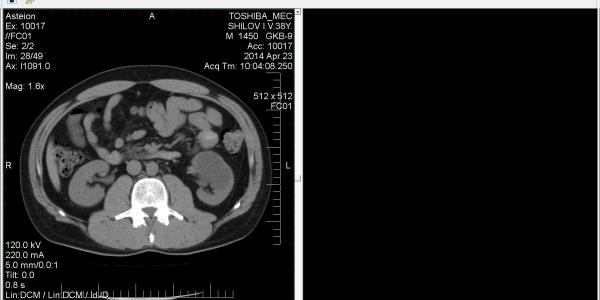

Нефрометрическая шкала R.E.N.A.L. позволяет прог